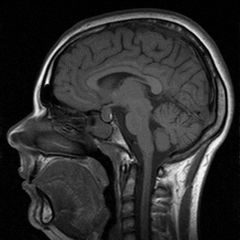

Метод магнитной томографии известен под несколькими названиями: магнитно-резонансная томография, ядерный резонанс, магнитно-ядерная томография. Эти названия отражают суть метода: диагностика, основанная на явлении ядерного резонанса, возникающего под влиянием магнитного поля. Несмотря на такое устрашающее для людей, не связанных с физикой, название, этот метод стал прорывом в аппаратной диагностике, и в настоящее время считается наиболее информативным методом медицинской визуализации.

С помощью метода магнитной томографии можно получить изображение любых внутренних сред организма, причем изображение послойное и очень точное, что позволяет достоверно определять не только размеры, но и местоположение, скажем, опухоли или кисты, и ее взаимодействие с соседними органами. Благодаря этому магнитная томография широко используется в нейрологии, с ее помощью диагностируют большинство заболеваний головного и спинного мозга.

Вообще стоит сказать, что метод магнитного резонанса настолько информативен и безопасен, что его можно применять практически во всех случаях диагностики болезней внутренних органов. Пожалуй, единственное, что препятствует его еще более широкому, чем в настоящее время, использованию, это довольно высокая стоимость исследования, поскольку весьма дорогой является аппаратура для его проведения. Тем не менее, сейчас вопрос «где сделать хорошее МРТ?» обычно уже не стоит, поскольку каждое крупное медицинское учреждение располагает такой возможностью.